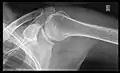

شانهها

تصویر AP سطح اریب خلفی ۴۰ درجه پس از Grashey

بدن باید حدود ۳۰ تا ۴۵درجه نسبت به شانه چرخانده شود تا تصویربرداری انجام شود و بیمار در حالت ایستاده یا نشسته اجازه میدهد دستانش را آویزان کند. این روش شکاف مفصلی و تراز عمودی نسبت به حفرات را نشان میدهد.[16]